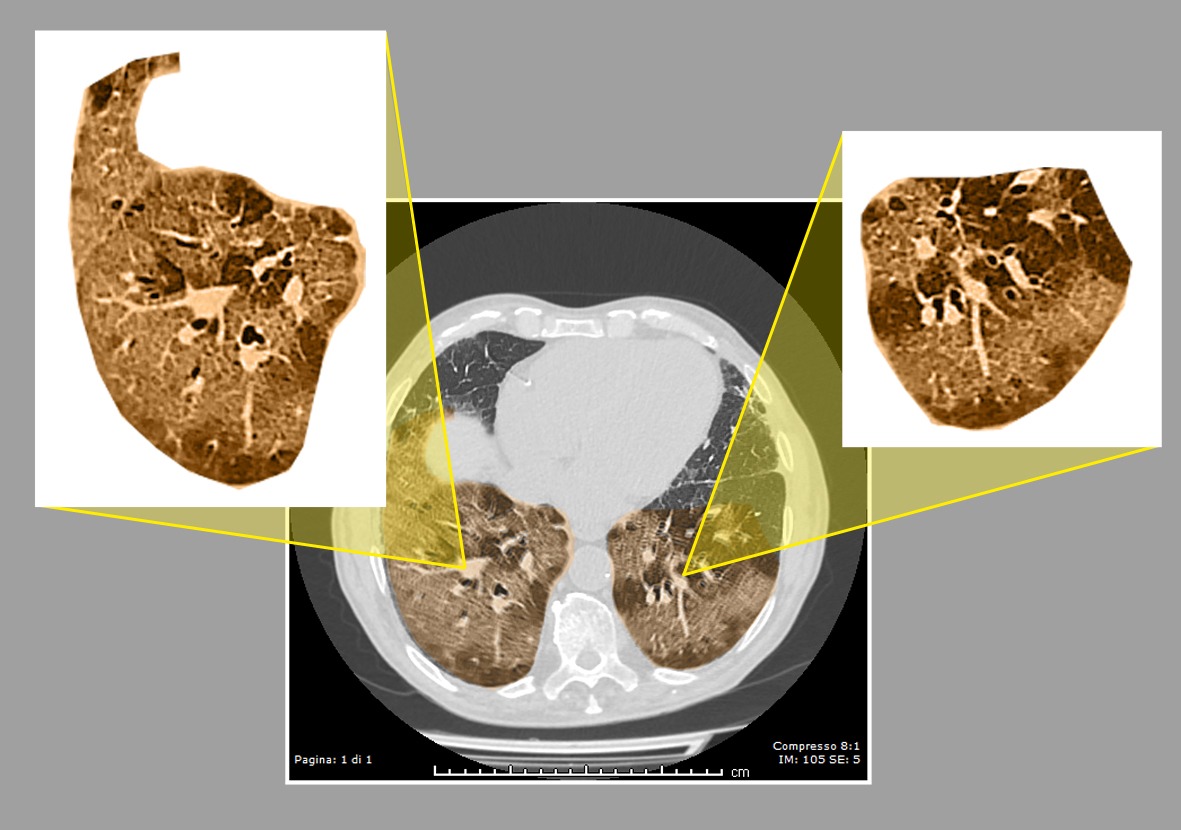

Un recente studio coordinato dalle Unità Operative di Medicina Interna e Neurologia dell’IRCCS Casa Sollievo della Sofferenza e pubblicato sulla rivista “Diagnostics”[1] ha valutato l’affidabilità della diagnosi radiologica e clinica, misurandone l’accuratezza rispetto ad un successivo esame sierologico, in un campione di pazienti ricoverati presso l’ospedale per sospetto Covid-19, ma con tamponi nasofaringei molecolari negativi.

L’analisi dei dati è avvenuta dopo la raccolta di un campione di siero, per la determinazione della sierologia anti-Sars-Cov-2, ottenuto dopo almeno 15 giorni dal ricovero o durante follow-up dei pazienti. I dati dei pazienti sono quindi stati valutati da un team di radiologi e di clinici, senza fornire loro i risultati sierologici. I radiologi, all’oscuro delle cartelle cliniche dei pazienti, hanno rivalutato in modo indipendente le Tac del torace; allo stesso modo, i clinici hanno valutato indipendentemente le cartelle cliniche e stabilito la probabilità della diagnosi di Covid-19.

“Al giorno d’oggi, la necessità di isolare e trattare rapidamente un numero elevato di pazienti affetti da insufficienza respiratoria da Covid-19 richiede una modulazione delle attività ospedaliere al fine di garantire la limitazione del rischio di trasmissione virale ad altri pazienti e al personale sanitario”, spiega Salvatore De Cosmo, direttore dell’Unità di Medicina Interna dell’IRCCS Casa Sollievo della Sofferenza. “Tuttavia, confermare o escludere con certezza una diagnosi di Covid-19 è di fondamentale importanza per una corretta allocazione e per prevenire la diffusione virale intraospedaliera. I nostri dati confermano che le valutazioni radiologiche e cliniche identificano correttamente la maggior parte dei pazienti Covid-19 ed escludono la maggior parte dei pazienti non affetti, essendo sufficientemente accurate e affidabili per consentire una diagnosi di Covid-19 in pazienti con ripetuti tamponi negativi”, conclude Maurizio Leone, direttore dell’Unità di Neurologia dell’IRCCS Casa Sollievo della Sofferenza.